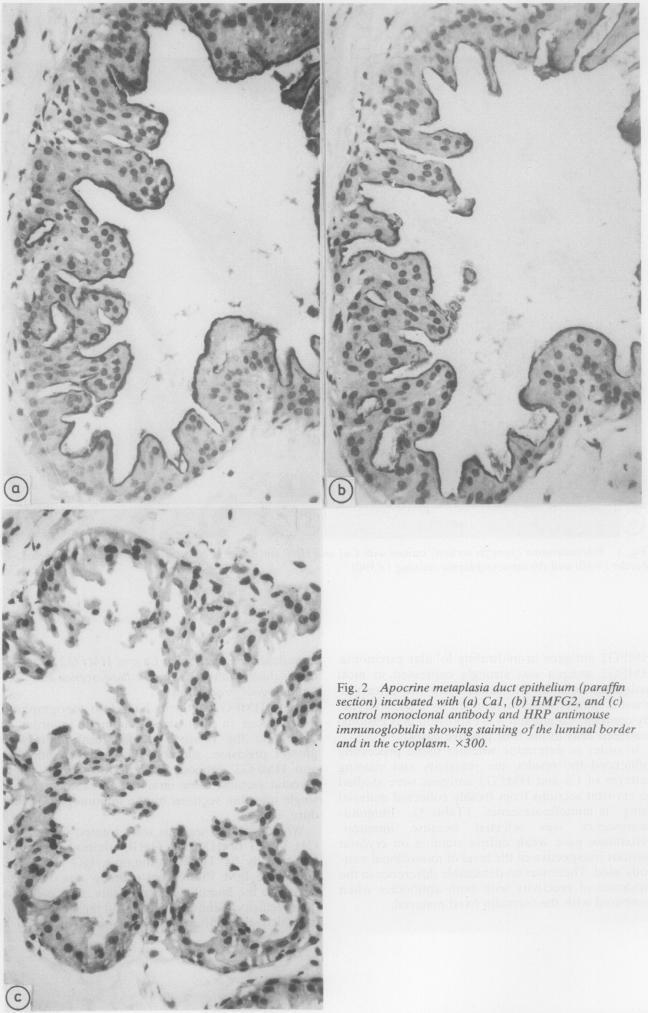

The reactivities of Ca1 and HMFG2 monoclonal antibodies were compared on paraffin wax embedded breast tissues using indirect immunoperoxidase. The expression of Ca antigen, like HMFG2, is not exclusive to malignancy: Ca was present in 41/53 (77%) and HMFG2 in 42/53 (79.2%) non-malignant conditions and both were present in 33/35 (94%) carcinomas. Similar results were obtained when cryostat sections were used. Both antigens showed striking similarities in their topographical distributions, although quantitative differences were seen. Their cellular and sub-cellular localisations were investigated by double labelling immunofluorescence and immunogold electron microscopy, which showed that the expression of Ca and HMFG2 antigens was closely associated on cell membranes but that the epitopes were distinct.

使用间接免疫过氧化物酶法,在石蜡包埋的乳腺组织上比较了Ca1和HMFG2单克隆抗体的反应性。与HMFG2一样,Ca抗原的表达并非恶性肿瘤所特有:在41/53(77%)的非恶性病变中存在Ca,在42/53(79.2%)的非恶性病变中存在HMFG2,在33/35(94%)的癌组织中两者均存在。当使用冰冻切片时也获得了类似结果。尽管存在数量差异,但两种抗原在其拓扑分布上显示出惊人的相似性。通过双重标记免疫荧光和免疫金电子显微镜研究了它们的细胞和亚细胞定位,结果表明Ca和HMFG2抗原的表达在细胞膜上密切相关,但表位是不同的。